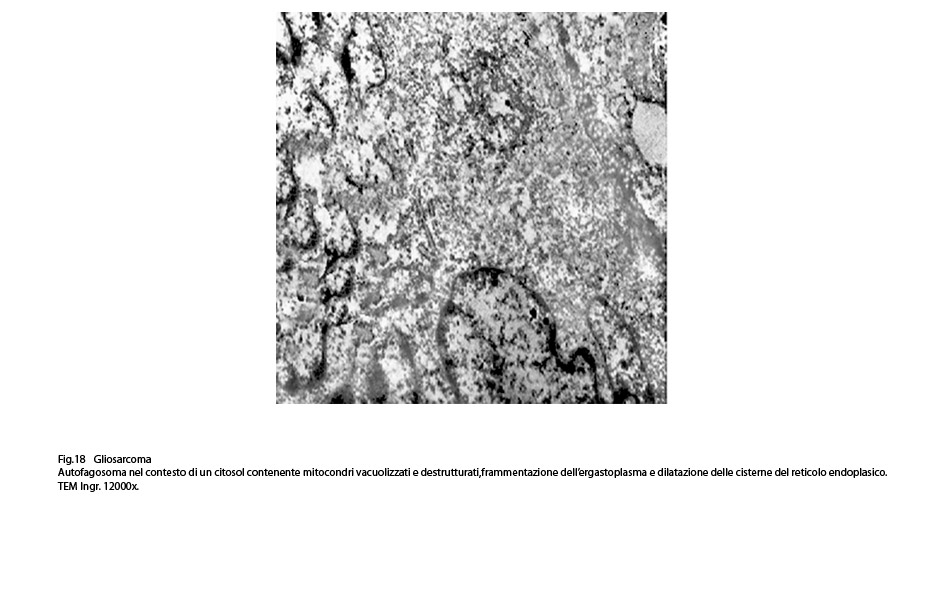

L’autofagosoma è un focolaio vescicoloso endocellulare,di diverse dimensioni,di forma sferoidale,delimitato da una membrana a doppio strato;al suo interno si ritrovano materiali biologici eterogenei di aspetto granuloso,filamentoso,amorfo,tubulare e nei focolai voluminosi anche organelli citoplasmatici o frammenti nucleari.

Nel citoplasma delle cellule di gliosarcoma esaminate sono stati riscontrati con frequenza focolai di autofagosomi e di autolisosomi; i primi si riconoscono quali corpi ovoidali o rotondeggianti i quali sono demarcati da una membrana a doppio contorno e contengono nel loro spazio cavo materiale granuloso,filamentoso ed amorfo; i secondi,gli autolisosomi, sono delimitati da una membrana a monostrato,spesso notevolmente ispessita per sovrapposizione di materiale amorfo;il loro contenuto è rappresentato da materiale biologico in varie fasi di degradazione.

Fig.18  Fig.19